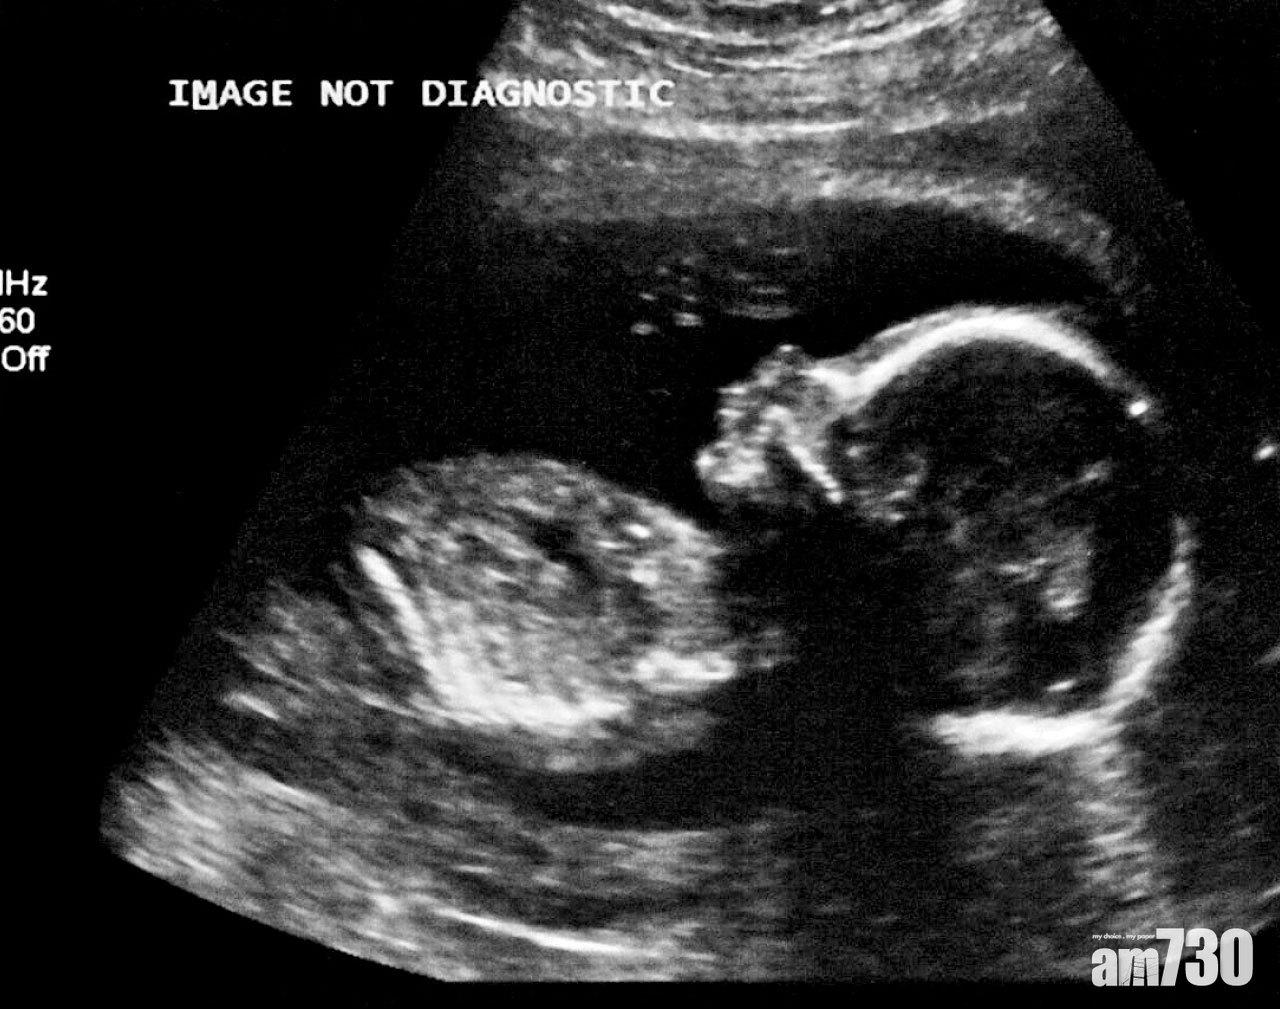

法研究首次證實胎兒可經由母體感染。(資料圖片、美聯社)

國際科學期刊《自然通訊》(Nature Communications)周二發表報告指,巴黎一名孕婦3月24日入住安托萬貝克萊爾醫院(Antoine Béclère Hospital)治療新冠肺炎,當時她懷孕35周,住院3日後,醫生發現胎兒心跳異常須剖腹生產;男嬰出生後血液及肺部液體驗出病毒,3日後更出現易怒、不肯進食及痙攣等,其後逐漸康復,毋須用藥。全球多地早有初生嬰兒染疫病例,但一直難以確定從母體、生產期間抑或出生後從環境感染。醫院兒科主任德盧卡指,今次醫療團隊抽取胎盤、羊水、臍帶血及母親和嬰兒的血液作化驗,證實病毒可經胎盤傳給胎兒。